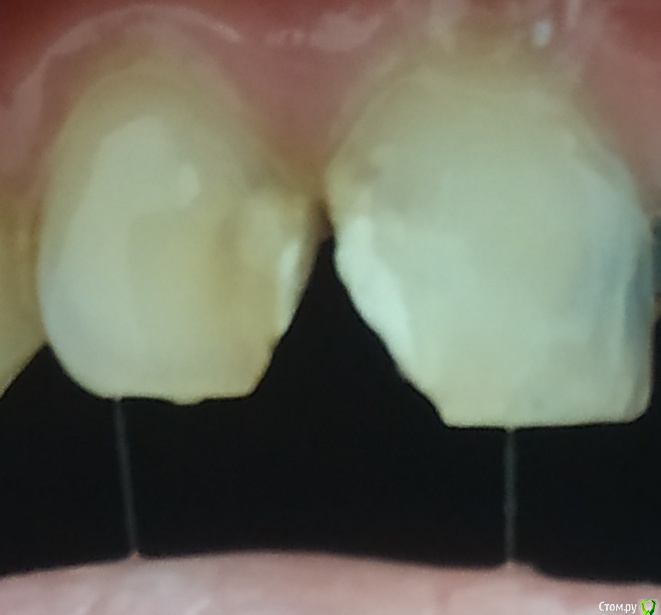

Andrian Опубликовано 19 июля, 2019 Поделиться Опубликовано 19 июля, 2019 (изменено) Зубы депульпированы по причине поражения межзубным кариесом. Изнутри врач убрал пораженные ткани, примерно треть обоих зубов. Спереди осталась тонкая стенка. В данный момент стоит временная пломба. Выглядит будто на некотором расстоянии от очага есть темный ореол. Его врач не убрал. Это нормально или это так пломба просвечивается? Изменено 19 июля, 2019 пользователем Andrian Ссылка на комментарий

red_butler Опубликовано 20 июля, 2019 Поделиться Опубликовано 20 июля, 2019 По этой фотографии ответить невозможно, скорее всего Вы видите границу полости. Это не важно, коронки это перекроют 1 Ссылка на комментарий

Andrian Опубликовано 20 июля, 2019 Автор Поделиться Опубликовано 20 июля, 2019 скорее всего Вы видите границу полости дело в том что это "радуга" была видна и до вмешательства. И после осталась в том же месте. Очень похоже что это потемнение самих тканей, но довольно далеко от эпицентра. Вот и беспокоит не станет ли это потемнение очагом вторичного кариеса. Или подобное потемнение может имеет несколько иную природу и беспокоиться не о чем? Ссылка на комментарий

DmitrySH Опубликовано 20 июля, 2019 Поделиться Опубликовано 20 июля, 2019 дело в том что это "радуга" была видна и до вмешательства. И после осталась в том же месте. Очень похоже что это потемнение самих тканей, но довольно далеко от эпицентра. Вот и беспокоит не станет ли это потемнение очагом вторичного кариеса. Или подобное потемнение может имеет несколько иную природу и беспокоиться не о чем? Ткани могут быть пигментированы от кариеса. Но не все что пигментировано - то надо убирать, если эти ткани плотные, то можно оставить.Далее уже вопрос в том как зуб восстановить. Если это будут коронки, то не принципиально. Ссылка на комментарий

Andrian Опубликовано 20 июля, 2019 Автор Поделиться Опубликовано 20 июля, 2019 Ткани могут быть пигментированы от кариеса. Но не все что пигментировано - то надо убирать, если эти ткани плотные, то можно оставить. Большое спасибо. Это и хотелось узнать, возможно ли такое. А эстетика меня не сильно волнует, в кино мне не сниматься, да и если не присматриваться не особо и видно. Планируются пломбы. Ссылка на комментарий

DmitrySH Опубликовано 20 июля, 2019 Поделиться Опубликовано 20 июля, 2019 Пломбы при таком разрушении - не надежный вариант. 2 Ссылка на комментарий